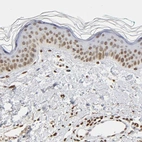

Immunohistochemical staining of human Fallopian tube shows moderate nuclear positivity in glandular cells.